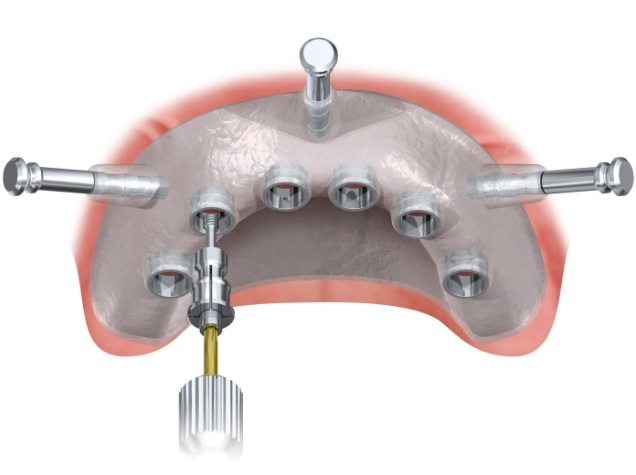

- Mucosa-supported guides

- Designed for fully edentulous patients with sufficient soft tissue coverage

- Allow for flapless surgery, reducing post-operative discomfort

- Often incorporate fixation pins to prevent movement during surgery

- May require additional stabilization techniques in cases with mobile mucosa

The effectiveness of a surgical guide depends on its design parameters:

- Guide extension and support:

- Tooth-supported guides should cover at least 3-4 stable teeth

- Mucosa-supported guides require 2-3mm tissue contact area for pressure distribution

- Bone-supported guides need a secure fit with a 2mm border around osteotomy sites

- Sleeve parameters and adjustments:

- Inner Diameter (ID): Typically 2.0-5.0mm based on drill system compatibility

- Outer Diameter (OD): Usually 4.5-6.0mm for adequate guide strength

- Height: Between 5-10mm depending on available vertical space

- Offset: 0-3mm to control drill depth relative to implant position

- Additional design considerations:

- Incorporation of ventilation holes (3-4mm diameter) to prevent vacuum effects

- Minimum 1mm clearance from gingival margins to prevent tissue impingement

- Adequate thickness for structural integrity during surgery